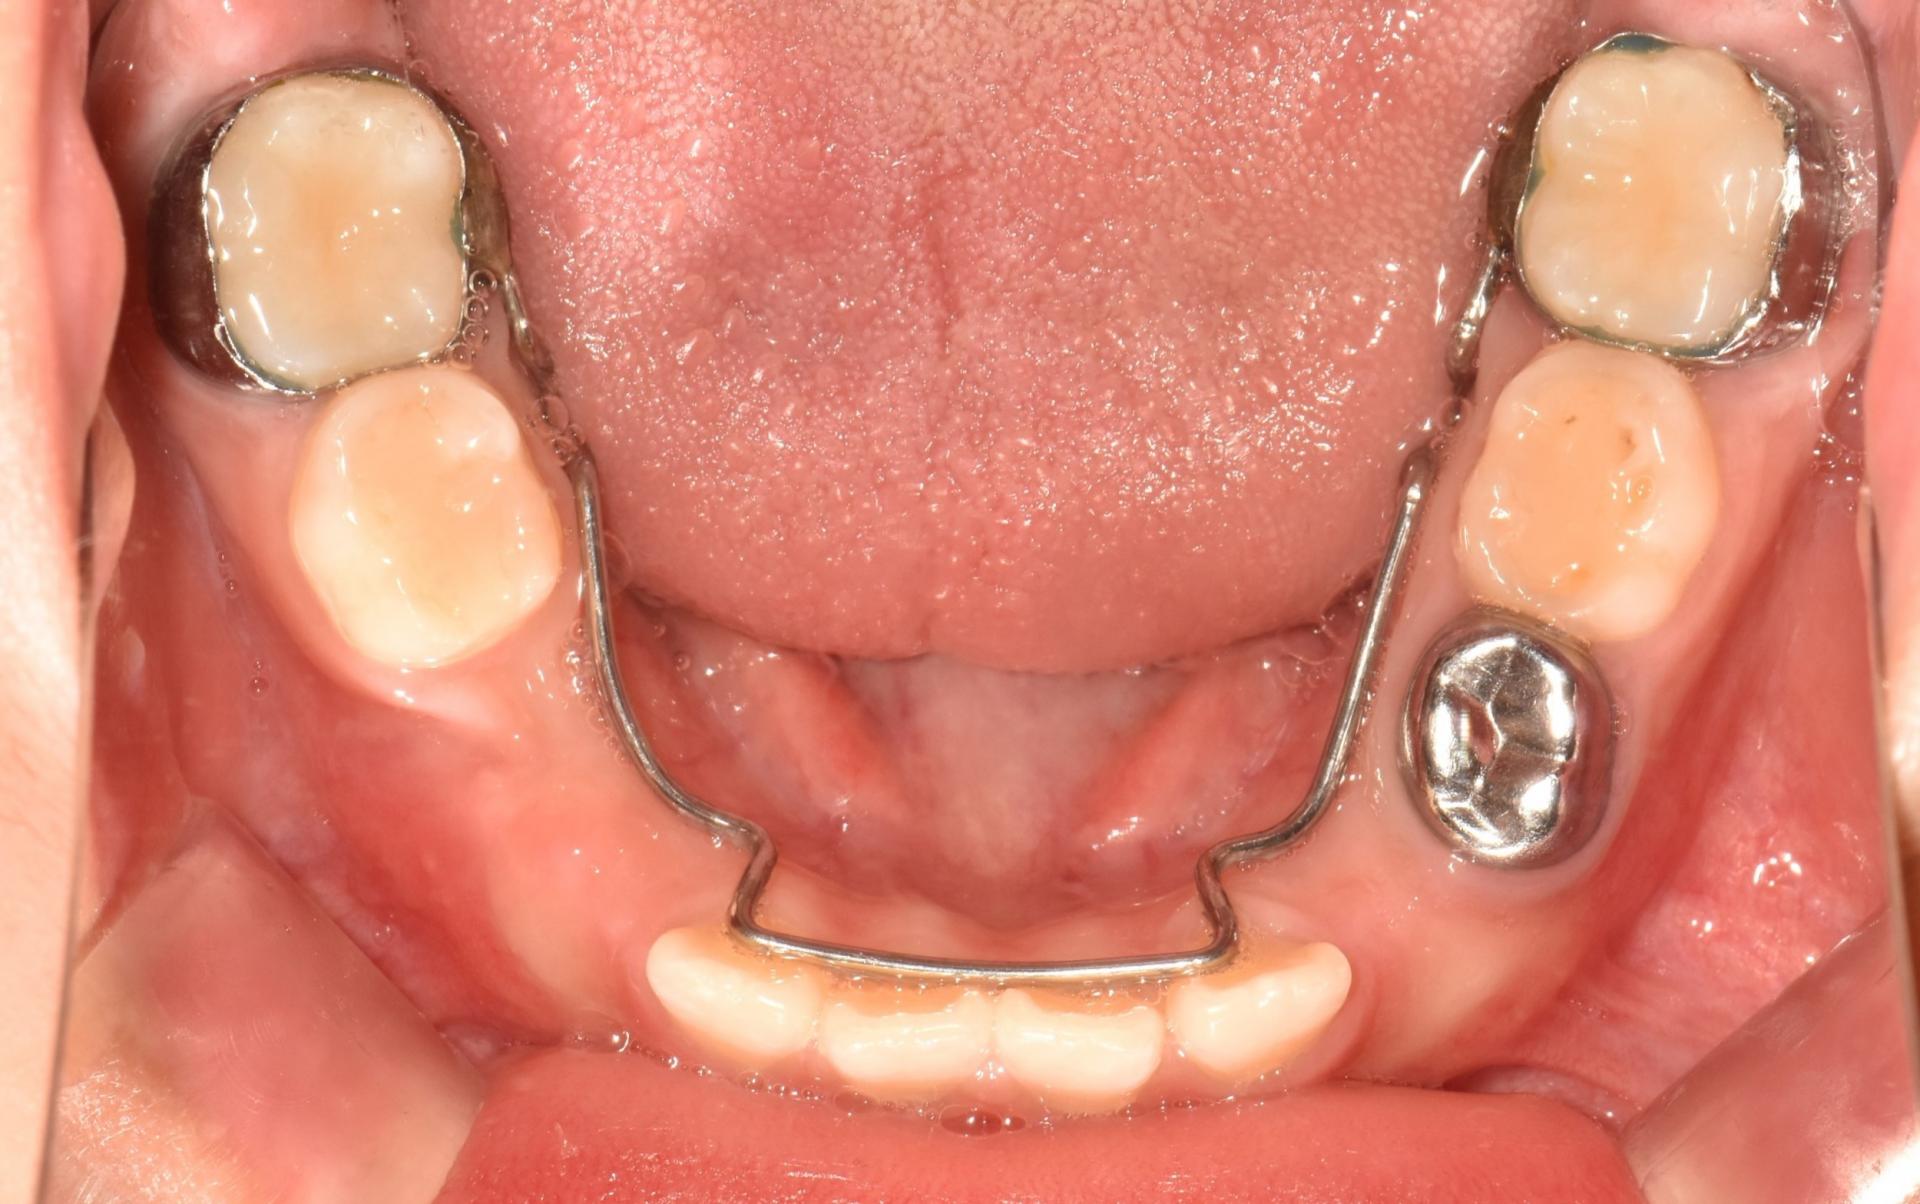

치료 전 구강 내 사진입니다 .

앞니가 벌어져 있고, 치아가 나올 공간이 부족합니다. 앞니끼리 서로 부딪히고 있네요.